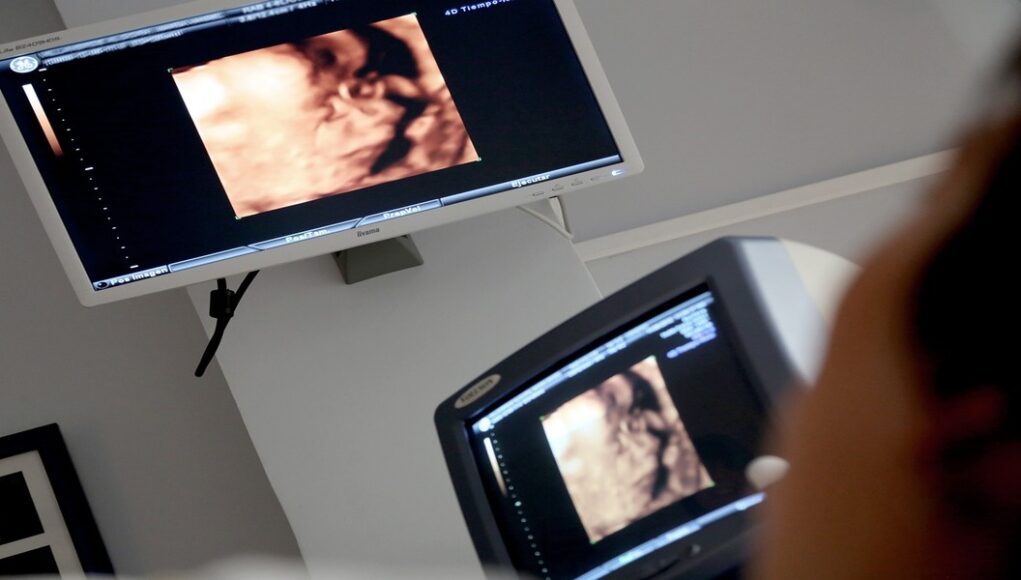

L’ecografia è un esame diagnostico che utilizza gli ultrasuoni per ottenere immagini degli organi interni del corpo. E’ uno degli strumenti più utilizzati nei più svariati ambiti clinici, in quanto considerato esame di primo livello, cioè il primo a cui viene sottoposto un individuo nel sospetto di una qualche patologia.

Non è assolutamente un esame di tipo invasivo, poiché l’ecografia non utilizza radiazioni ionizzanti, infatti è totalmente innocuo ed è anche consigliato per monitorare il feto delle donne in gravidanza.

L’utilità è diversa e in molti campi della medicina, ad esempio per la prevenzione e la diagnosi dei tumori, per indagare su ogni possibile degenerazione dei tessuti e organi. Inoltre l’ecografia viene utilizzata per indagare sullo stato di tendini e muscoli, quindi al fine di identificare infiammazioni o degenerazioni di tendini o lesioni muscolari.